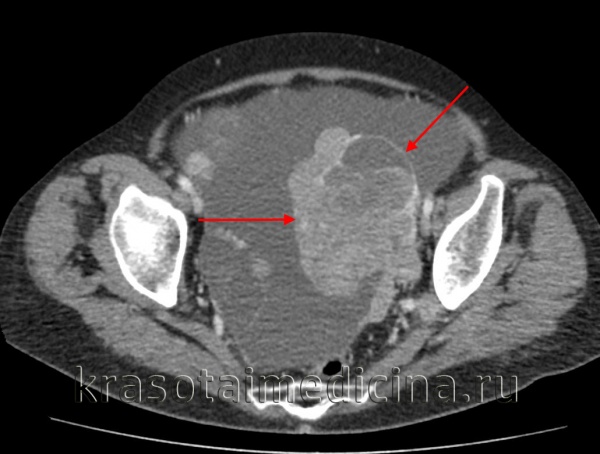

(Слева) При КТ с контрастным усилением в аксиальной плоскости у девушки 15 лет с пальпируемой в животе опухолью в тазу выявляется объемное образование, неравномерно накапливающее контрастное вещество.

(Справа) При КТ с контрастным усилением в корональной плоскости у той же пациентки в тазу видна опухоль, неравномерно накапливающая контрастное вещество. Полученное изображение в отсутствие жировой ткани и очагов обызвествления неспецифично. При патологоанатомическом исследовании диагностирована незрелая тератома высокой степени злокачественности.